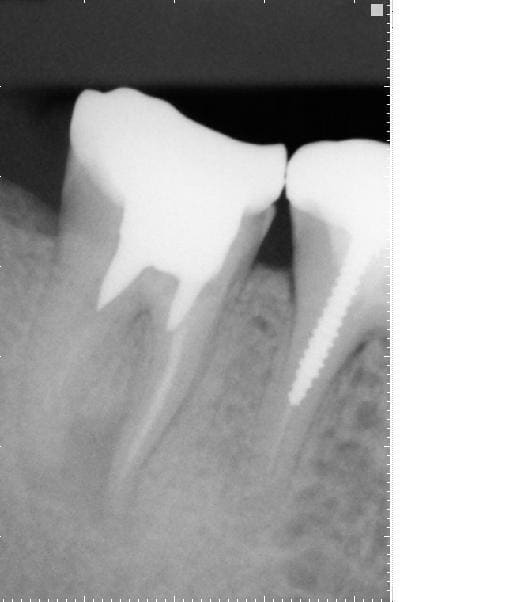

Raté puisque je finis à l'instant une reprise d'endo + kyste surinfecté sous coiffe richemont 47 scellée au verre iono (et racines sans traitement endo notable mais obturées au même verre iono, un plaisir)..... 3/4 d'heure ce matin et 1h 30 de plus ce soir mais je l'ai eue.... merci lokki et les huiles essentielles :0)

ps: le faux canal de taille de l'ancrage sur endo refaite c'est pas moi....

Richemont kkeetx - Eugenol

Reprise endo auvqay - Eugenol